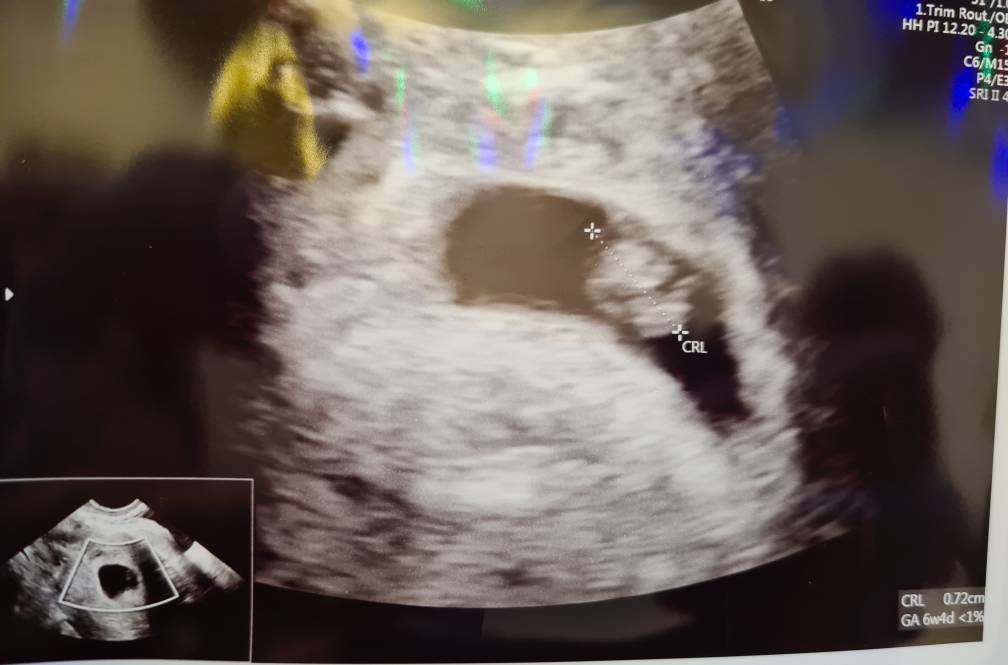

Moje maleństwo 7.2mm z serduszkiem! [emoji173] wg usg 6t4d, czyli 12dni do tyłu w stosunku do ostatniej miesiączki.

Jak siadałam na kozetce, to balam się patrzeć w stronę monitora, a pani doktor tylko chwile poszukała i od razu powiedziała że widać maleństwo, pierwsze co było widać to pulsujące serce. W ogóle lekarz uspokoila mnie z ta wielkością pecherzyka, bo właśnie przy pco i problemach z owulacja bardzo często zarodki pokazują się późno i nie ma co za wcześnie się stresować.

Mam dalej brać duphaston, euthyrox 25, glucophage j prenatal uno, ale dołożyła mi jeszcze luteinę (mam progesteron na granicy) i acard.

Do teraz cala się trzęsę, na chwilkę puściła dźwięk serduszka, to było piękne.